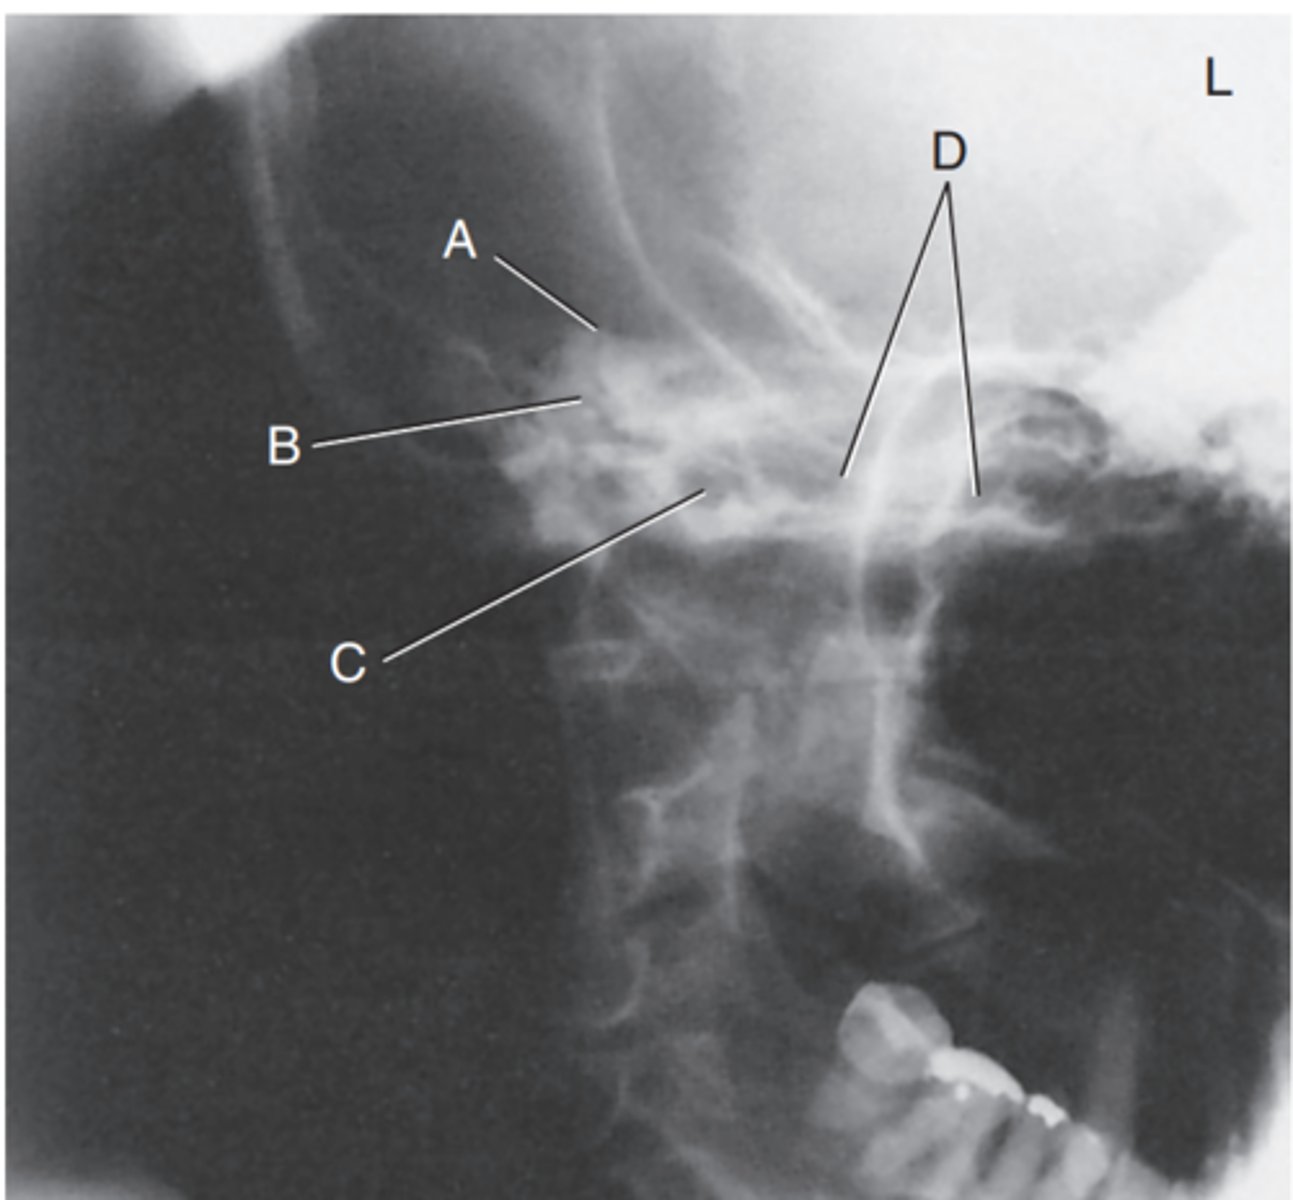

Label A

Mastoid antrum

Label B

Mastoid air cells

Label C

Downside mandibular condyle (just anterior to EAM)

Label D

Upside (magnified) mandibular condyle

Label E